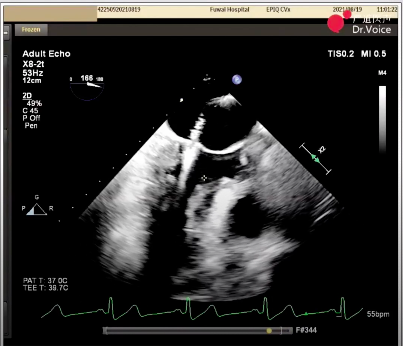

初次夹闭时二尖瓣前瓣夹闭部分偏少,调整位置后尝试夹闭,超声显示瓣夹一侧出现少量反流;松开瓣夹后再次调整位置,准确捕获并充分夹闭二尖瓣瓣叶,完成经导管缘对缘修复。

最终夹闭后的超声图像